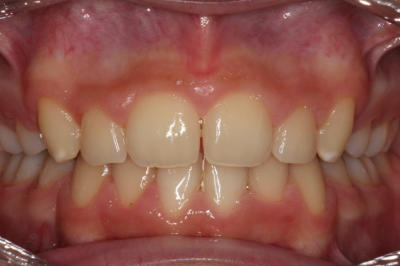

Crowding – Child case